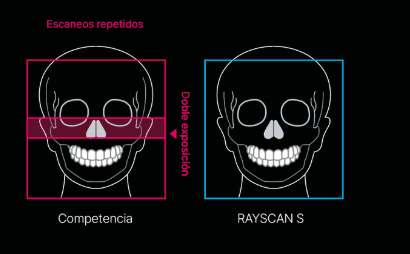

Sensor de tamaño real

Tradicionalmente, la práctica de unir imágenes era común para generar una imagen 3D de gran tamaño. Lamentablemente, éste enfoque produce distorsiones en la imagen, exigiendo mucho tiempo para el procesamiento de datos y reconstrucción de imágenes, haciendo que los resultados sean menos confiables clínicamente.

Ingrese a la tecnología de imágenes con sensor a tamaño real de RAYSCAN S, donde el clínico ahora puede adquirir resultados precisos, sin esfuerzo, sin la necesidad de unir imágenes. Ésta técnica, no sólo produce mágenes amplias sino que también prioriza minimizar la exposición a la radiación para la seguridad del

paciente.